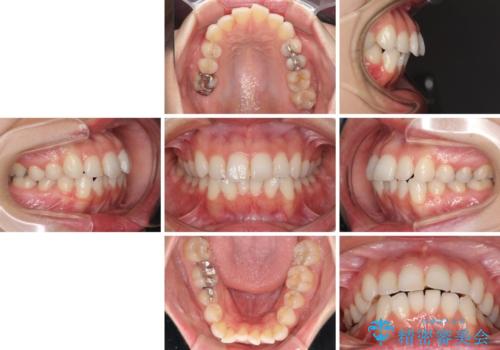

【モニター】前歯のデコボコをインビザラインできれいに整える

- 前歯のデコボコを気にして来院された患者様です。

主に下顎歯列全体の後方移動とIPR(歯と歯の間を削る)によってデコボコが解消するように設計し、インビザラインにより治療を行うこととしました。

舌突出癖がある方ですと、叢生が解消すると同時に前方に拡大されてしまいますが、ゴムかけをしっかりと行ってくださったこともあり、スッキリとした仕上がりとなりました。